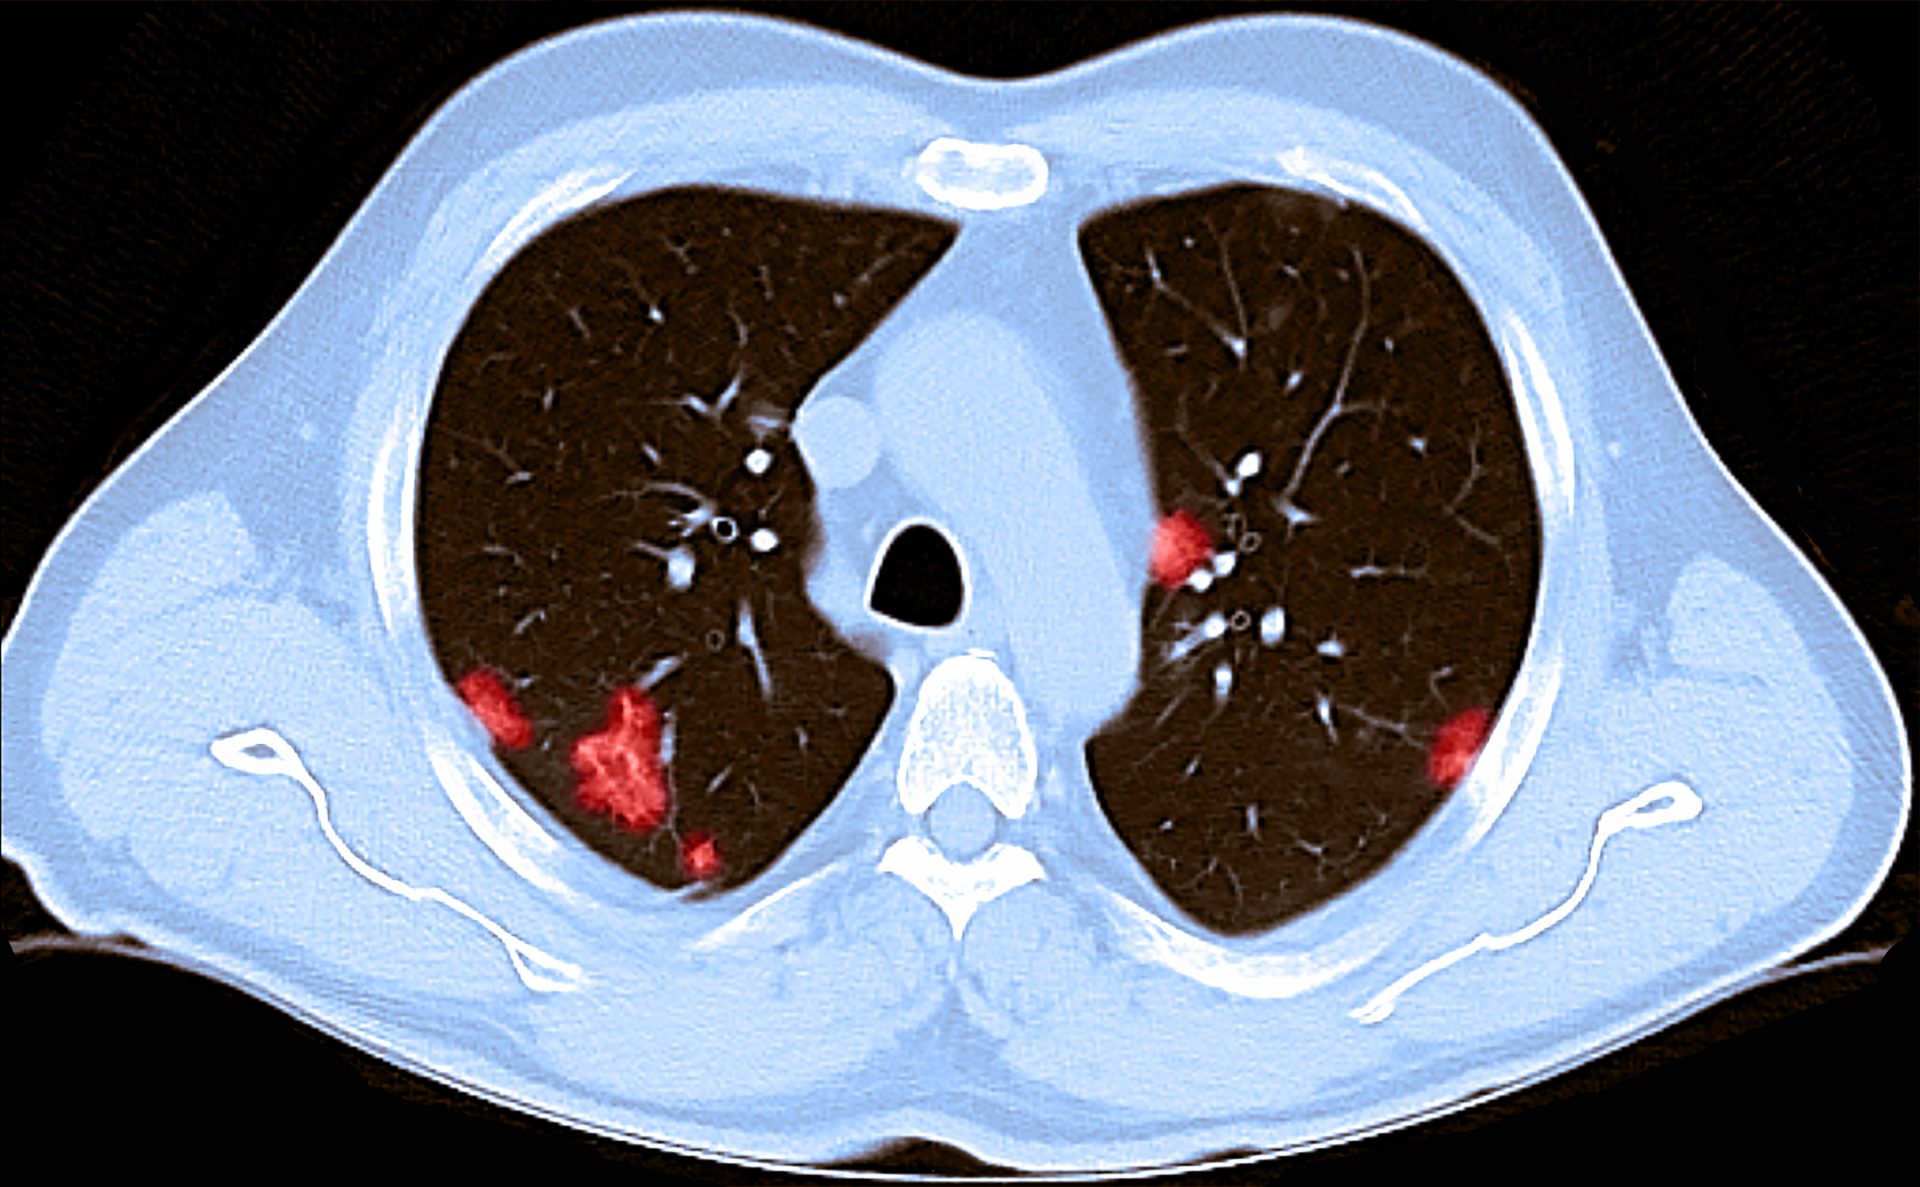

Headache, loss of smell, muscle pains, cough, sore throat, chest pain, no fever. It seems to start with a. Are chest pains a symptom of coronavirus? If your chest pain is intermittent or you have problems swallowing or have a fever and/or chills, you.